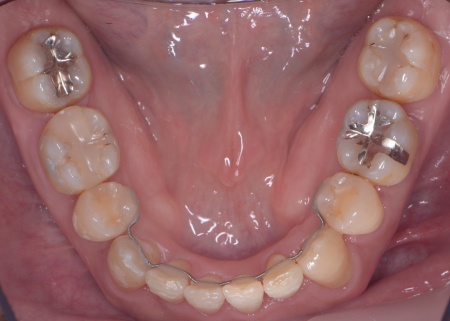

①抜歯をしてから歯並びを整える「抜歯矯正」 今回のケースでは、左上下の奥歯各1本(第3大臼歯)、右下の奥歯1本(第3大臼歯)、左上下と右下の奥歯各1本(第1小臼歯)の計6本の抜歯が必要です。 また、奥歯の噛み合わせは正常だったことから、それを維持しながら歯並びを整えるために以下の方法を採用します。 ②矯正治療後、歯周病を発症している左下奥歯(第1大臼歯)を温存するために、失われた骨や歯茎を再生する「歯周再生療法」を行う まずは歯の移動スペースを確保するために、計6本の歯を抜きます。 矯正治療終了後、歯の後戻りを防ぐため、上下前歯の裏側にワイヤーを接着して固定させる「フィックスリテーナー」を装着しています。 その後、左下奥歯に歯周再生療法を行って歯周病が改善したことを確認し、治療を終了しました。 |